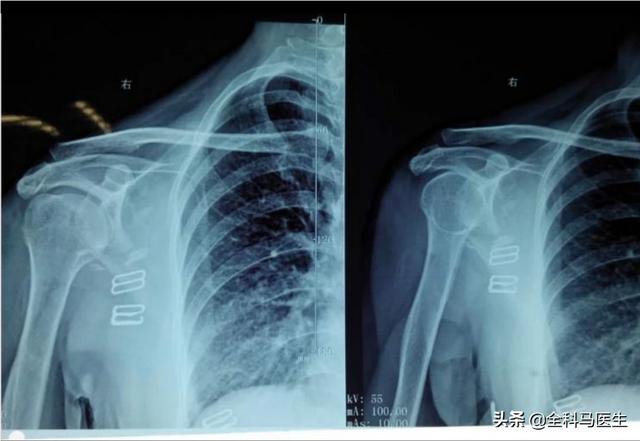

●hernie discale cervicale. Lorsqu'une hernie discale de la colonne cervicale appuie sur les nerfs, elle peut provoquer des douleurs à l'arrière de l'épaule, en particulier au niveau de l'épaule.Compression des racines nerveuses cervicales 6-7Il est possible de ressentir des douleurs autour de l'omoplate.

1, hernie discale, sténose spinale :Lorsque l'oppressionC4, C5, C6.Lorsque la racine du nerf est enfoncée, la douleur se situe au-dessus de l'os de l'épaule. Lorsqu'une pression est exercée sur la racine nerveuse, la douleur se situe au-dessus de l'os de l'épaule.C7, C8.Lorsque la racine nerveuse est enfoncée, la douleur se situe entre les omoplates. Lorsque la pression rencontre laC8La racine nerveuse, la douleur se situe dans les omoplates gauche et droite. La douleur peut être déclenchée en inclinant le cou vers l'arrière et en tournant la tête.。La douleur peut toucher le cou et la tête et le cou, ou irradier vers les doigts.

La spondylose cervicale est principalement causée par un travail de longue durée avec une tête basse, un oreiller trop haut et d'autres facteurs entraînant une dégénérescence et une protrusion des vertèbres cervicales, et une pression facile à travers les vaisseaux sanguins et les nerfs du cou, de sorte que lorsque le côté droit de la compression entraînera facilement une douleur et un engourdissement du côté droit de l'omoplate, et s'accompagnera de maux de tête et de vertiges, de douleurs cervicales et d'autres symptômes.